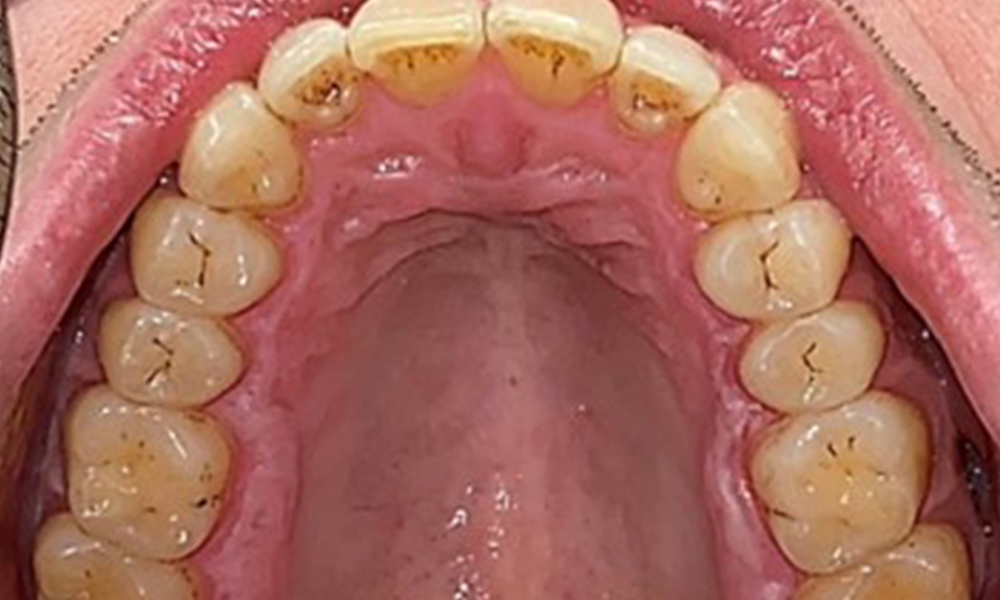

Occlusal view of the maxilla, © Dr R. Krapf

Fig. 3: Occlusal view of the maxilla, © Dr R. Krapf

Extraoral and intraoral findings

There were no pathological extraoral findings. During intraoral examination, inspection of the frontal view revealed brownish discolouration near the keratinised gingiva and at the transition to the moveable mucosa (Fig. 2), which could be attributed to nicotine consumption. Whitish mucosal lesions were observed on the palate, particularly near the maxillary molar palatal surfaces, indicating increased keratinisation and can also be attributed to nicotine consumption. The tongue was covered with a removable white and brownish coating.